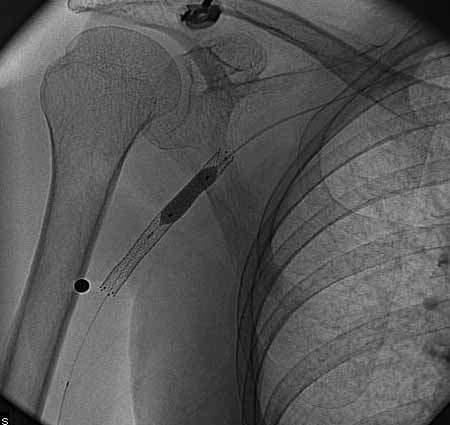

标题: DSA0091:肱动脉支架 [打印本页]

标题: DSA0091:肱动脉支架

女,66岁,右上肢无力.

图象清晰,做的很漂亮